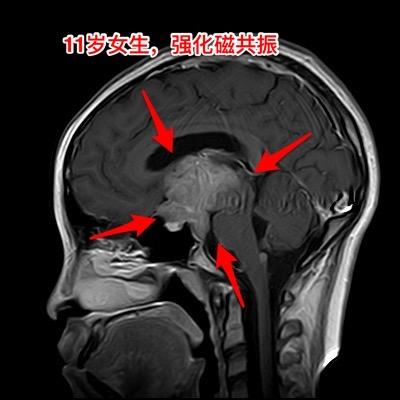

警惕小儿脑肿瘤。小孩子如果长了鞍区肿瘤,一般都会出现症状,一旦有了症状家长及医务人员就要足够重视,才能及时找到病因。 今天介绍的小孩子,肿瘤发现的就晚了。 11岁四川女孩子,因多饮多尿3年半,视力下降9个月,行走不稳、贪睡一个月发现鞍区肿瘤,急忙到北京来就医。 三年前开始出现多饮多尿症状,夜间上厕所好几次,到医院检查没有发现肾脏问题,就没有继续查找原因。 近两年身高增长缓慢,到医院化验显示生长激素缺乏,在当地医院注射生长激素治疗,没有查找生长激素